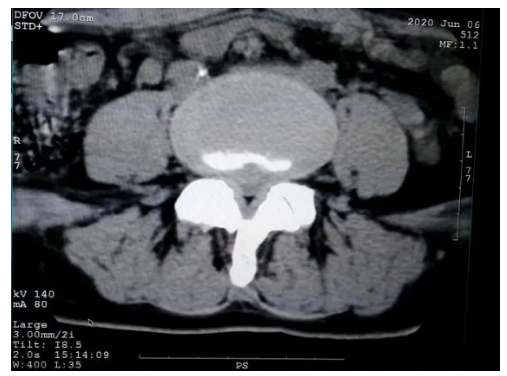

腰部CT拍片(L4-5椎间盘中央突出5mm)

前几日,张女士在他人推荐下听说五洲中医院针灸推拿科治疗“腰椎间盘突出症”效果不错,于是来到了五洲中医院就诊。经过对张女士看诊,张亚东医师根据其临床特点及四诊合参,认为张女士的症状当属“痹证”,伴有“气滞血瘀证”,并结合腰部CT拍片和腰部DR拍片等相关检查后,诊断为“腰椎间盘突出症”。